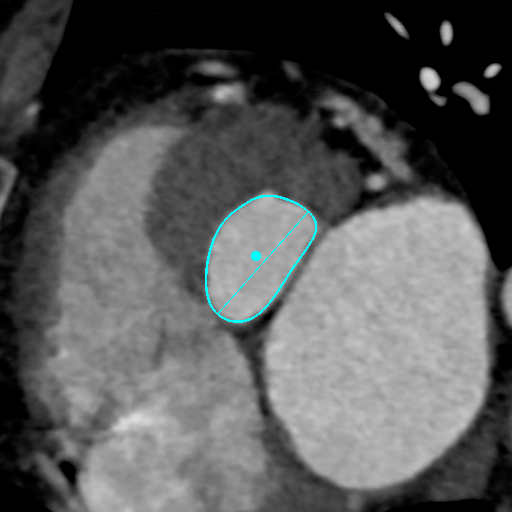

主动脉CT

主动脉瓣环平均直径:22.1mm;

左室流出道平均直径:23.7;

左冠脉开口:12.3mm;

右冠脉开口高度:11.2mm。

术前讨论:患者为三叶瓣主狭,左右冠瓣叶长,开口低,瓦氏窦小,左右冠高风险。

袁义强院长总结了该病例特点:三叶瓣,左右冠均高风险,解剖适合TAVR,年龄73岁,存在明确TAVR手术适应症。选择右股动脉入路,根据CT测量分析选择瓣膜大小,窦部情况可,瓣环平均直径22.1mm,计划22号球囊预扩,评估冠脉风险,选择植入24mm瓣膜。